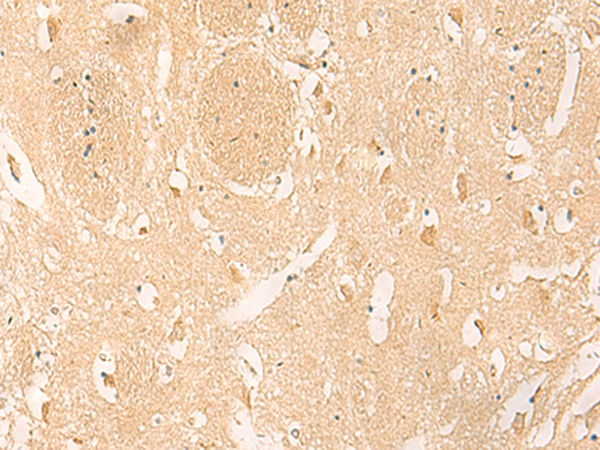

IHC positive control: |

Human tonsil and Human brain |